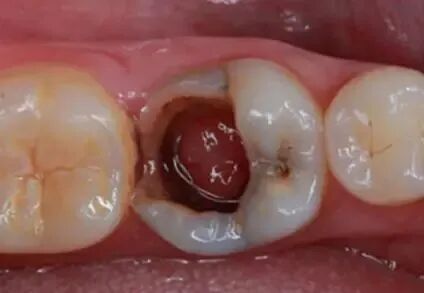

喺慢性增生性牙髓炎期間,患牙有好大嘅穿髓孔,同埋根尖孔夠粗大,牙髓血液運輸豐富,導致炎性牙髓組織生長成息肉狀態;經穿過髓孔凸出,多見於兒童、青少年。經常發生於乳磨牙或第一恆磨牙。噉,牙髓息肉有咩治療方法呢?

當查及患牙深洞有息肉時,臨床上還要與牙龈息肉和牙周膜息肉相鑒別。牙龈息肉多是牙龈乳頭向齲洞增生所致。牙周膜息肉發生于多根牙的齲損發展過程中,不但髓腔被穿通,tlimpJ,外界刺激令根分叉處嘅牙周膜反應性增生,息肉狀肉芽組織穿過髓底穿孔處入面髓腔,外觀好似牙髓息肉咁。

臨床病例展示

UcYdeH:

lVGXDN ↓

BevMTm

IUXgAa:

TNvQiT ↓

UcYdeH及IUXgAaXhNpgbG

封氫氧化鈣一周

一周後根管充填

去淨暫封物後樹脂充填